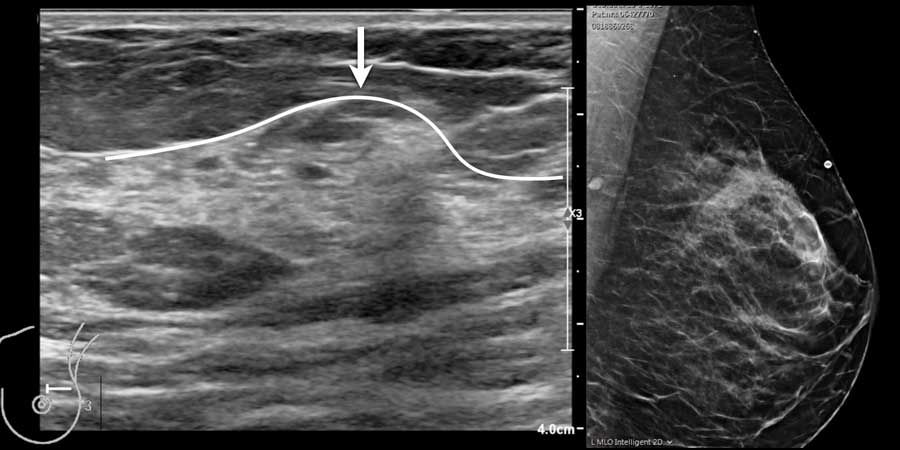

Trong cùng một tuyến vú có thể tồn tại các vùng có nhiều mô mỡ xen kẽ với các vùng chủ yếu là mô xơ tuyến, như có thể thấy trên video.

Khi quan sát đường bờ của mô tuyến (mũi tên), có thể hình dung rằng khi sờ nắn sẽ cảm thấy gồ ghề và đôi khi tạo cảm giác như có một khối u khi mô tuyến rất phát triển.

Mô tuyến sờ thấy được

Mô xơ tuyến không phân bố đều trong vú và thường tập trung nhiều hơn ở góc phần tư trên ngoài.

Đôi khi sự phì đại khu trú của mô tuyến có thể rất rõ rệt, tạo thành một khối u mà khi sờ nắn không thể phân biệt được với khối u thực sự.

Hình ảnh siêu âm cho thấy một vùng tập trung mô tuyến nằm trong nền mô mỡ của vú.

Do mô tuyến có độ chắc hơn mô mỡ, vùng này sẽ có cảm giác như một khối khi sờ nắn.

Chụp nhũ ảnh được thực hiện với đánh dấu vị trí khối sờ thấy và cũng cho thấy hình ảnh tập trung khu trú của mô tuyến bình thường.